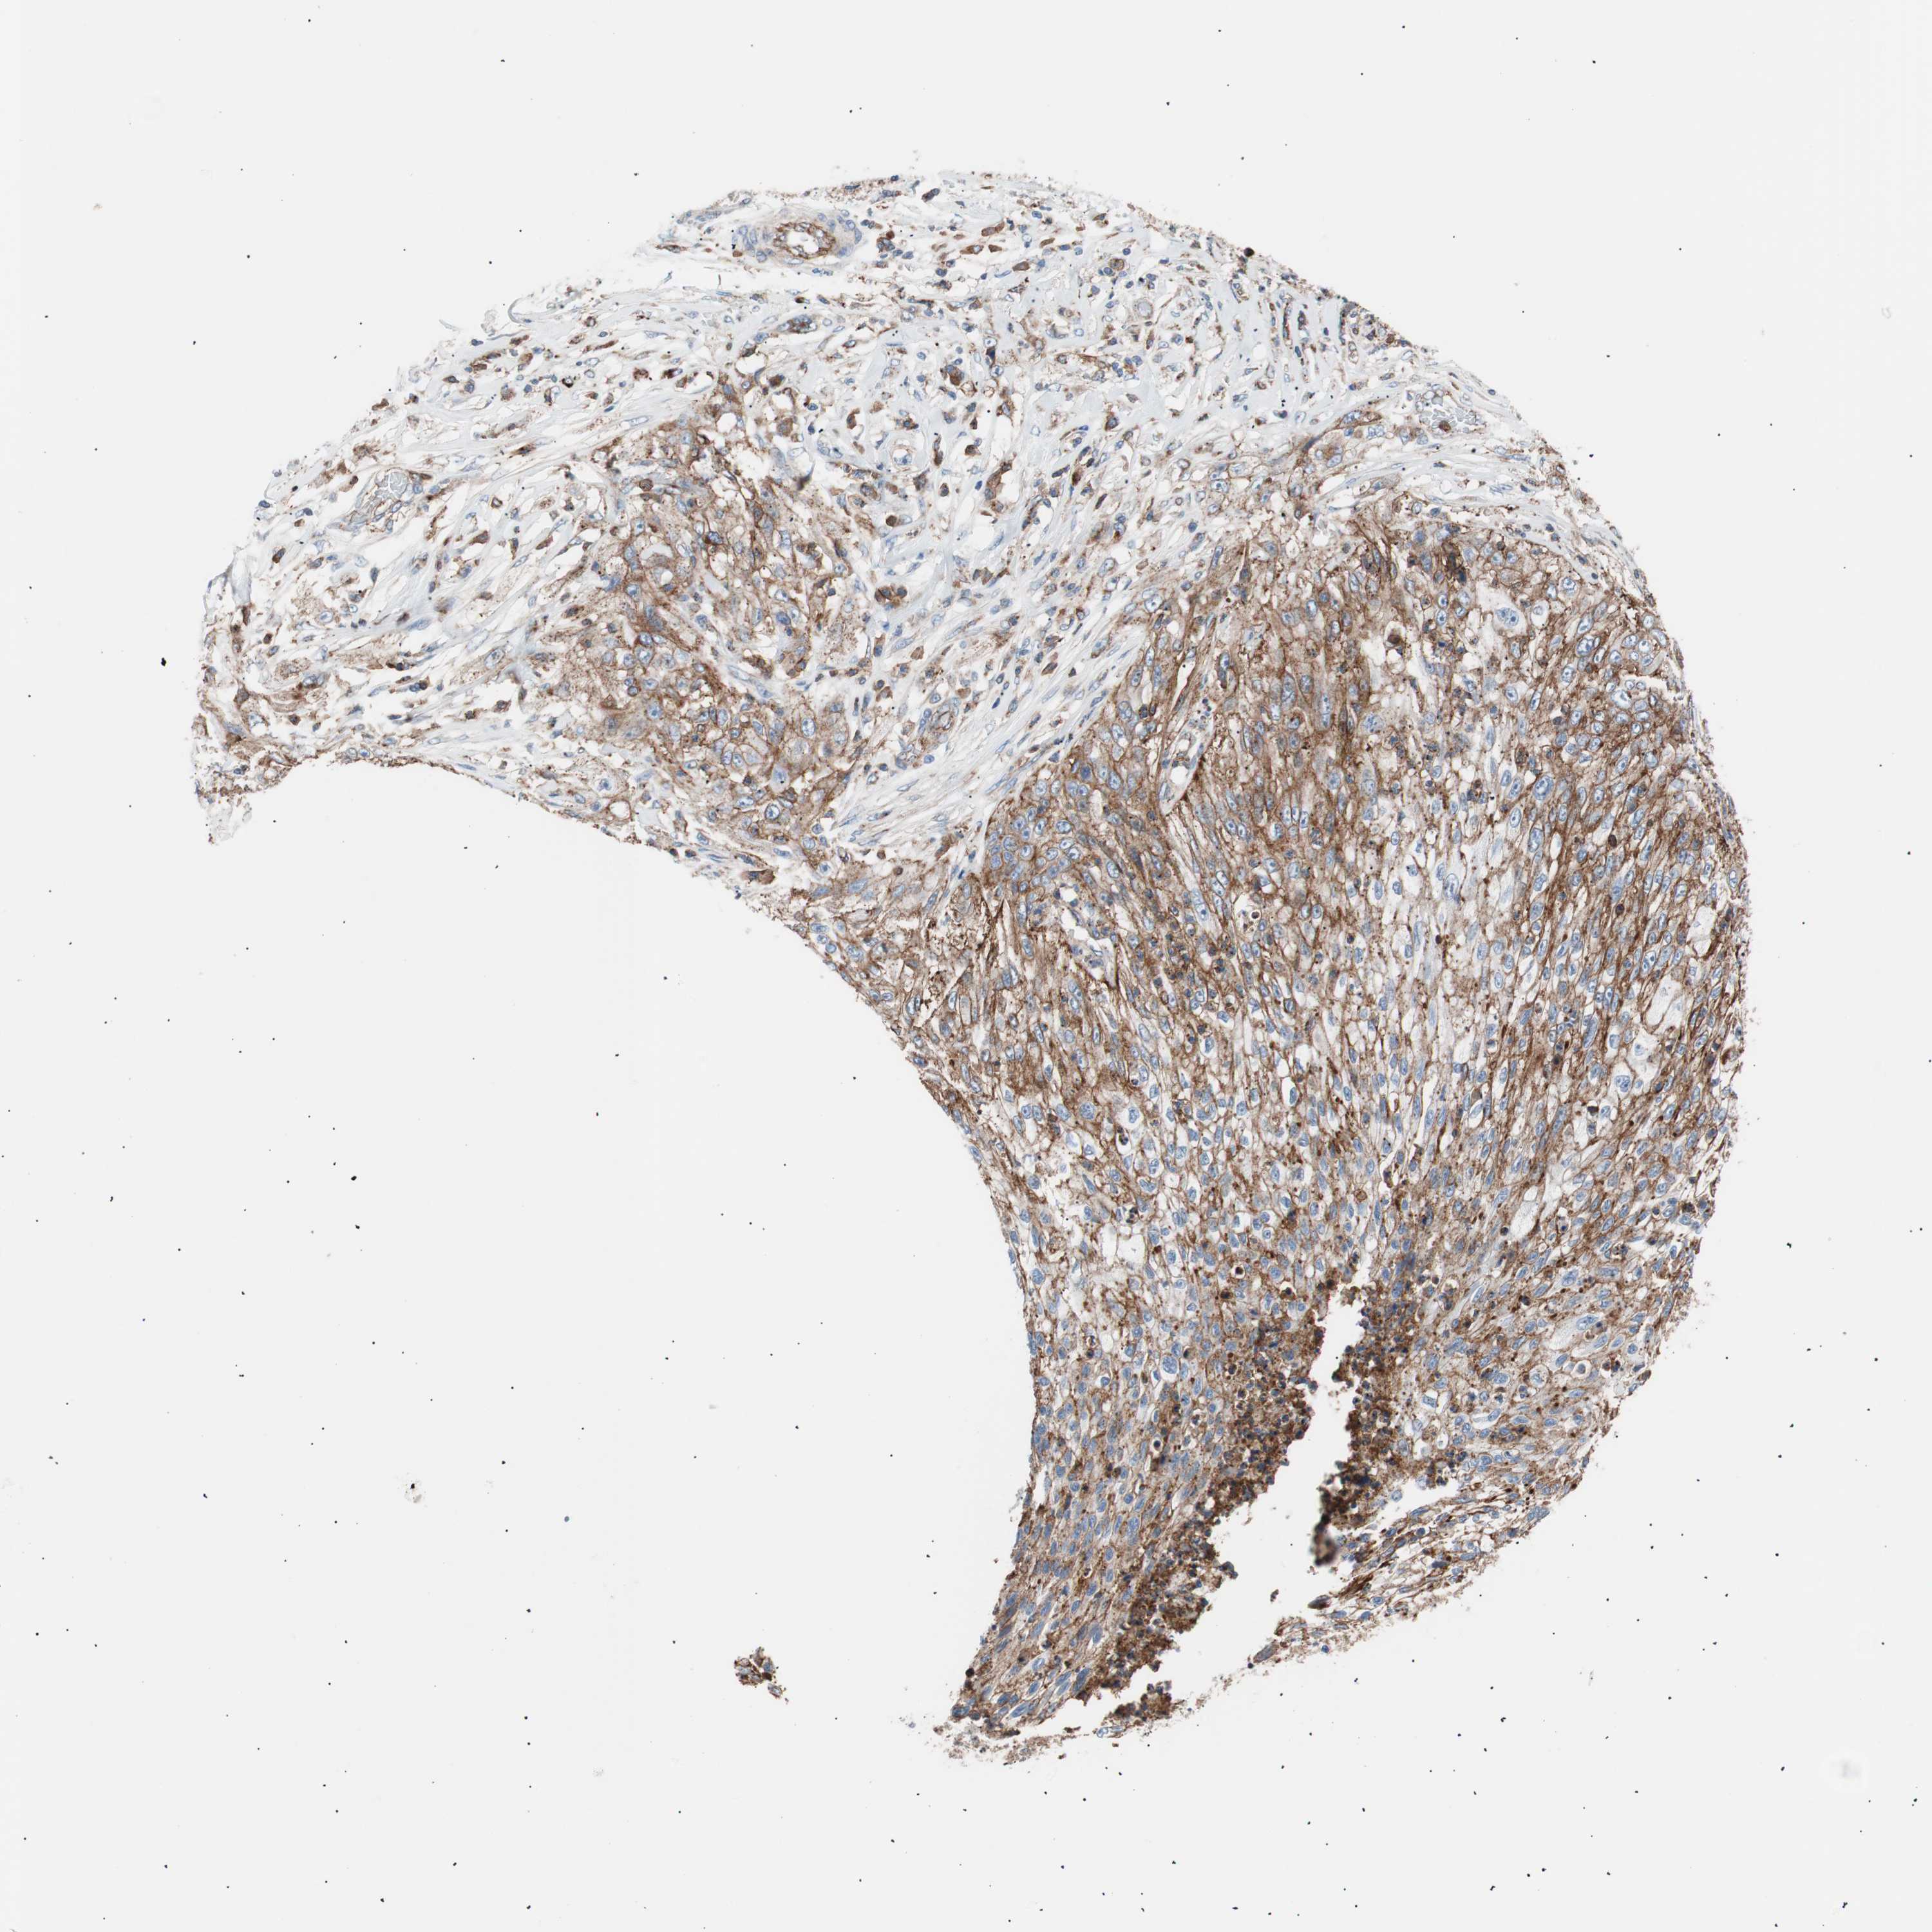

FLOT2

CANCER LUNG CANCER Show tissue menu